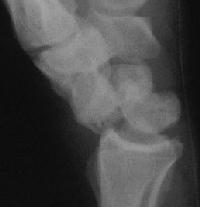

Case 5. Another,same bidirectional technique. Here, I ran the second screw too close to the first, and may have flattened the leading threads - not

ideal. The preop status:

Click for larger image